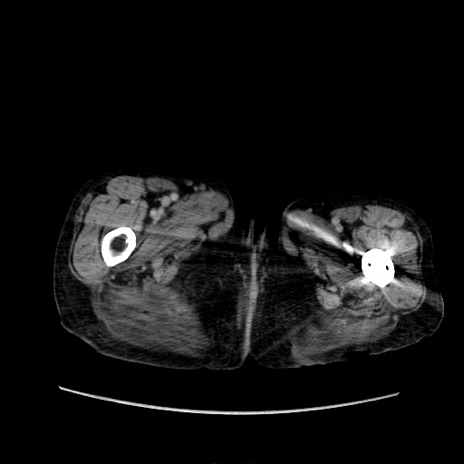

症例31(横断像)

【症例】80歳代 女性

【主訴】腹部膨満感

【現病歴】他院にて肝硬変にてフォロー中。1週間前から便秘、腹部膨満感、臍部腫瘤あり受診となる。

【既往歴】肝硬変

【身体所見】腹部膨隆あり、皮膚変化なし、疼痛なし。

【データ】WBC 4600、CRP 0.25